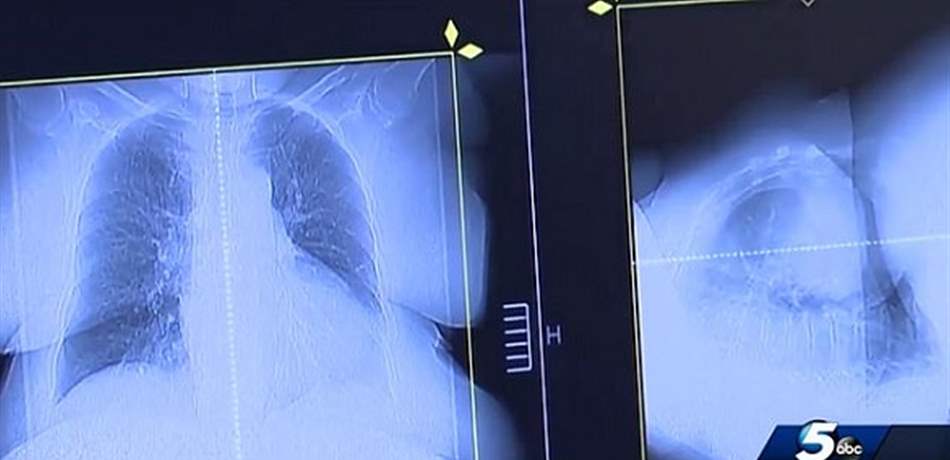

في قصة غريبة، لجأ أميركي إلى علاج غير تقليدي، ساعده على الشفاء من السرطان، بفضل عقار يستخدم عادة لعلاج الكلاب.في كانون الثاني 2017، كان جو تيبنس واثقاً من موته قريباً... |